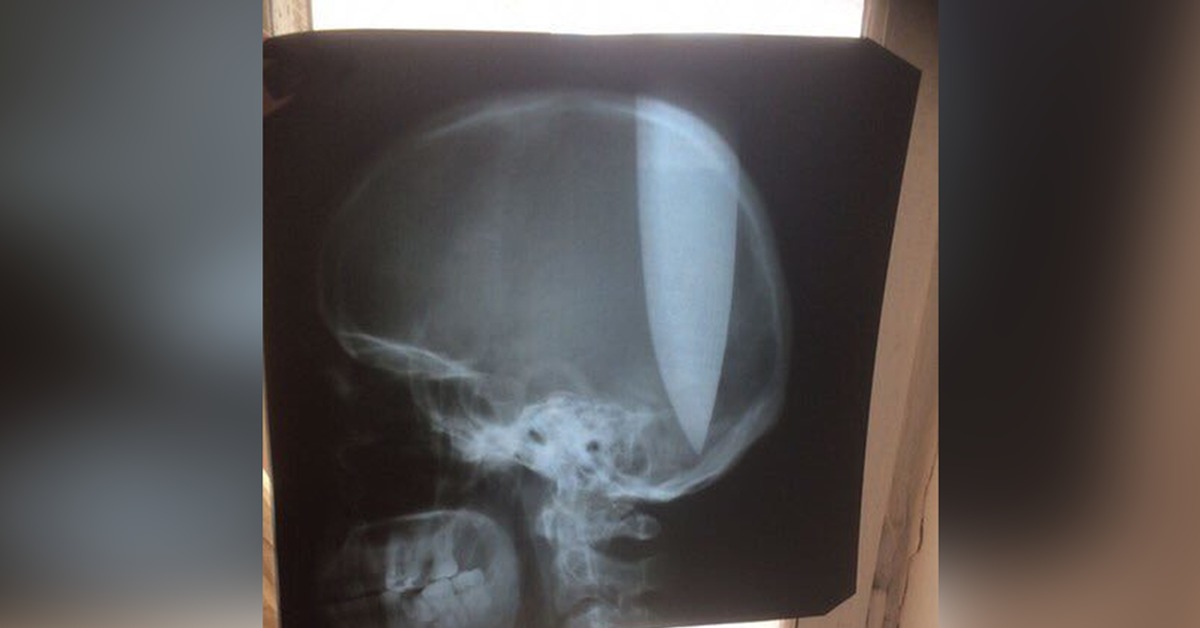

Фото Пробитых Голов

Фото Пробитых Голов 110 фото